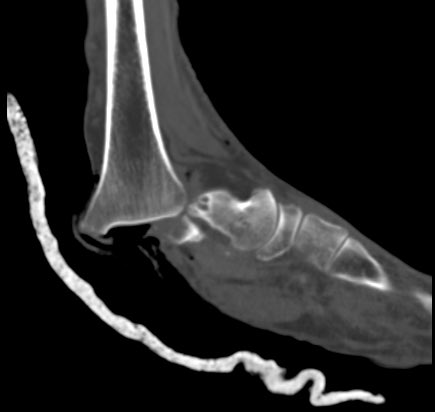

Clinical correlation needed

#exposedfracture#ortho#mskrad#radiologypic.twitter.com/BopZtsmPfI